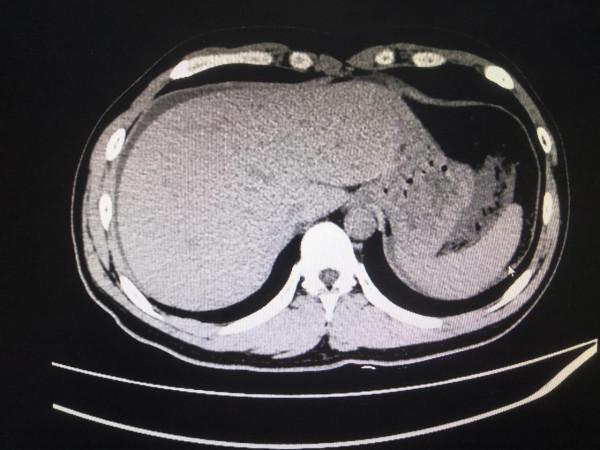

我跟過去做的,CT一掃下來,我就想到急性出血性胰腺炎。

回來診斷性腹穿抽出粉紅色腹水,送檢。

我直接了當的和父子倆說:住院有可能活,不住院一定會死,沒有商量的餘地。